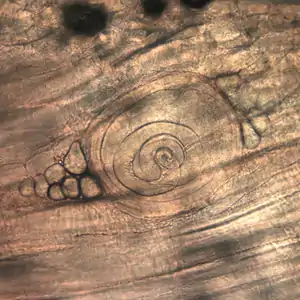

Trichinella larvae in pressed bear meat, partially digested with pepsin. The classic coil shape is visible. | |

- Trichinella spiralis larvae in muscle tissue